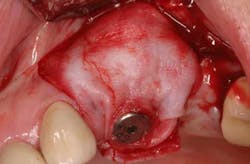

Mucograft® is an example of a xenograft material that has been used in lieu of autogenous grafts to increase keratinized tissue around dental implants (21). Made of porcine collagen, this material has a compact outer layer that can be left exposed to the oral environment and a spongy inner layer that facilitates a blood clot and promotes angiogenesis. A major advantage in using this material for increasing keratinized tissue around dental implants is that it can be used in challenging areas with little to no attached soft tissue because primary closure over this graft material is not needed and it can be left exposed (Figs. 3a-3c).

Fig. 3b: Soft tissue Mucograft placed at the time of implant surgery in order to augment keratinized tissue height and thickness. Primary closure was not obtained over this graft.

Fig. 3c: Final restorations showing a large increase in the height of keratinized tissue, facilitating oral hygiene and increasing plaque resistance.